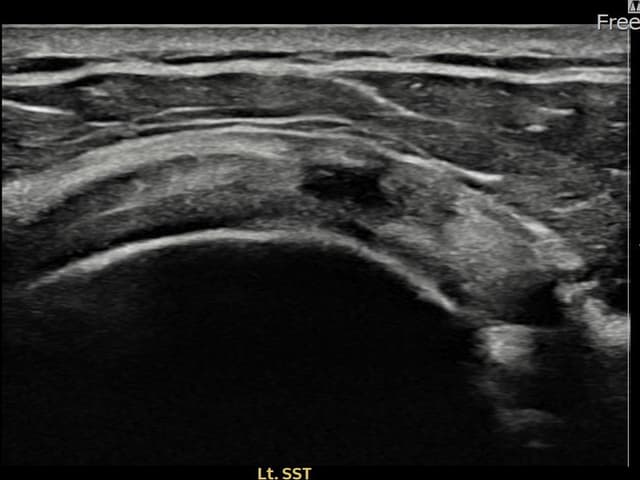

[촬영시기:23.07.18~23.09.14]

[어깨인대 축소봉합술] 좌측 어깨 광범위 파열로 수술을 권유받았으나 비수술 치료를 원해 내원하셨습니다.